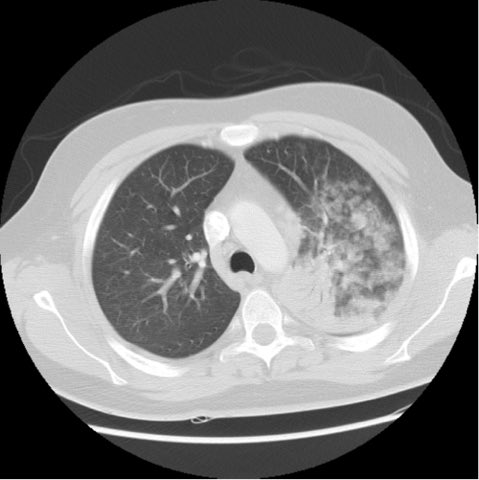

CXR below

11/ Chest CT below